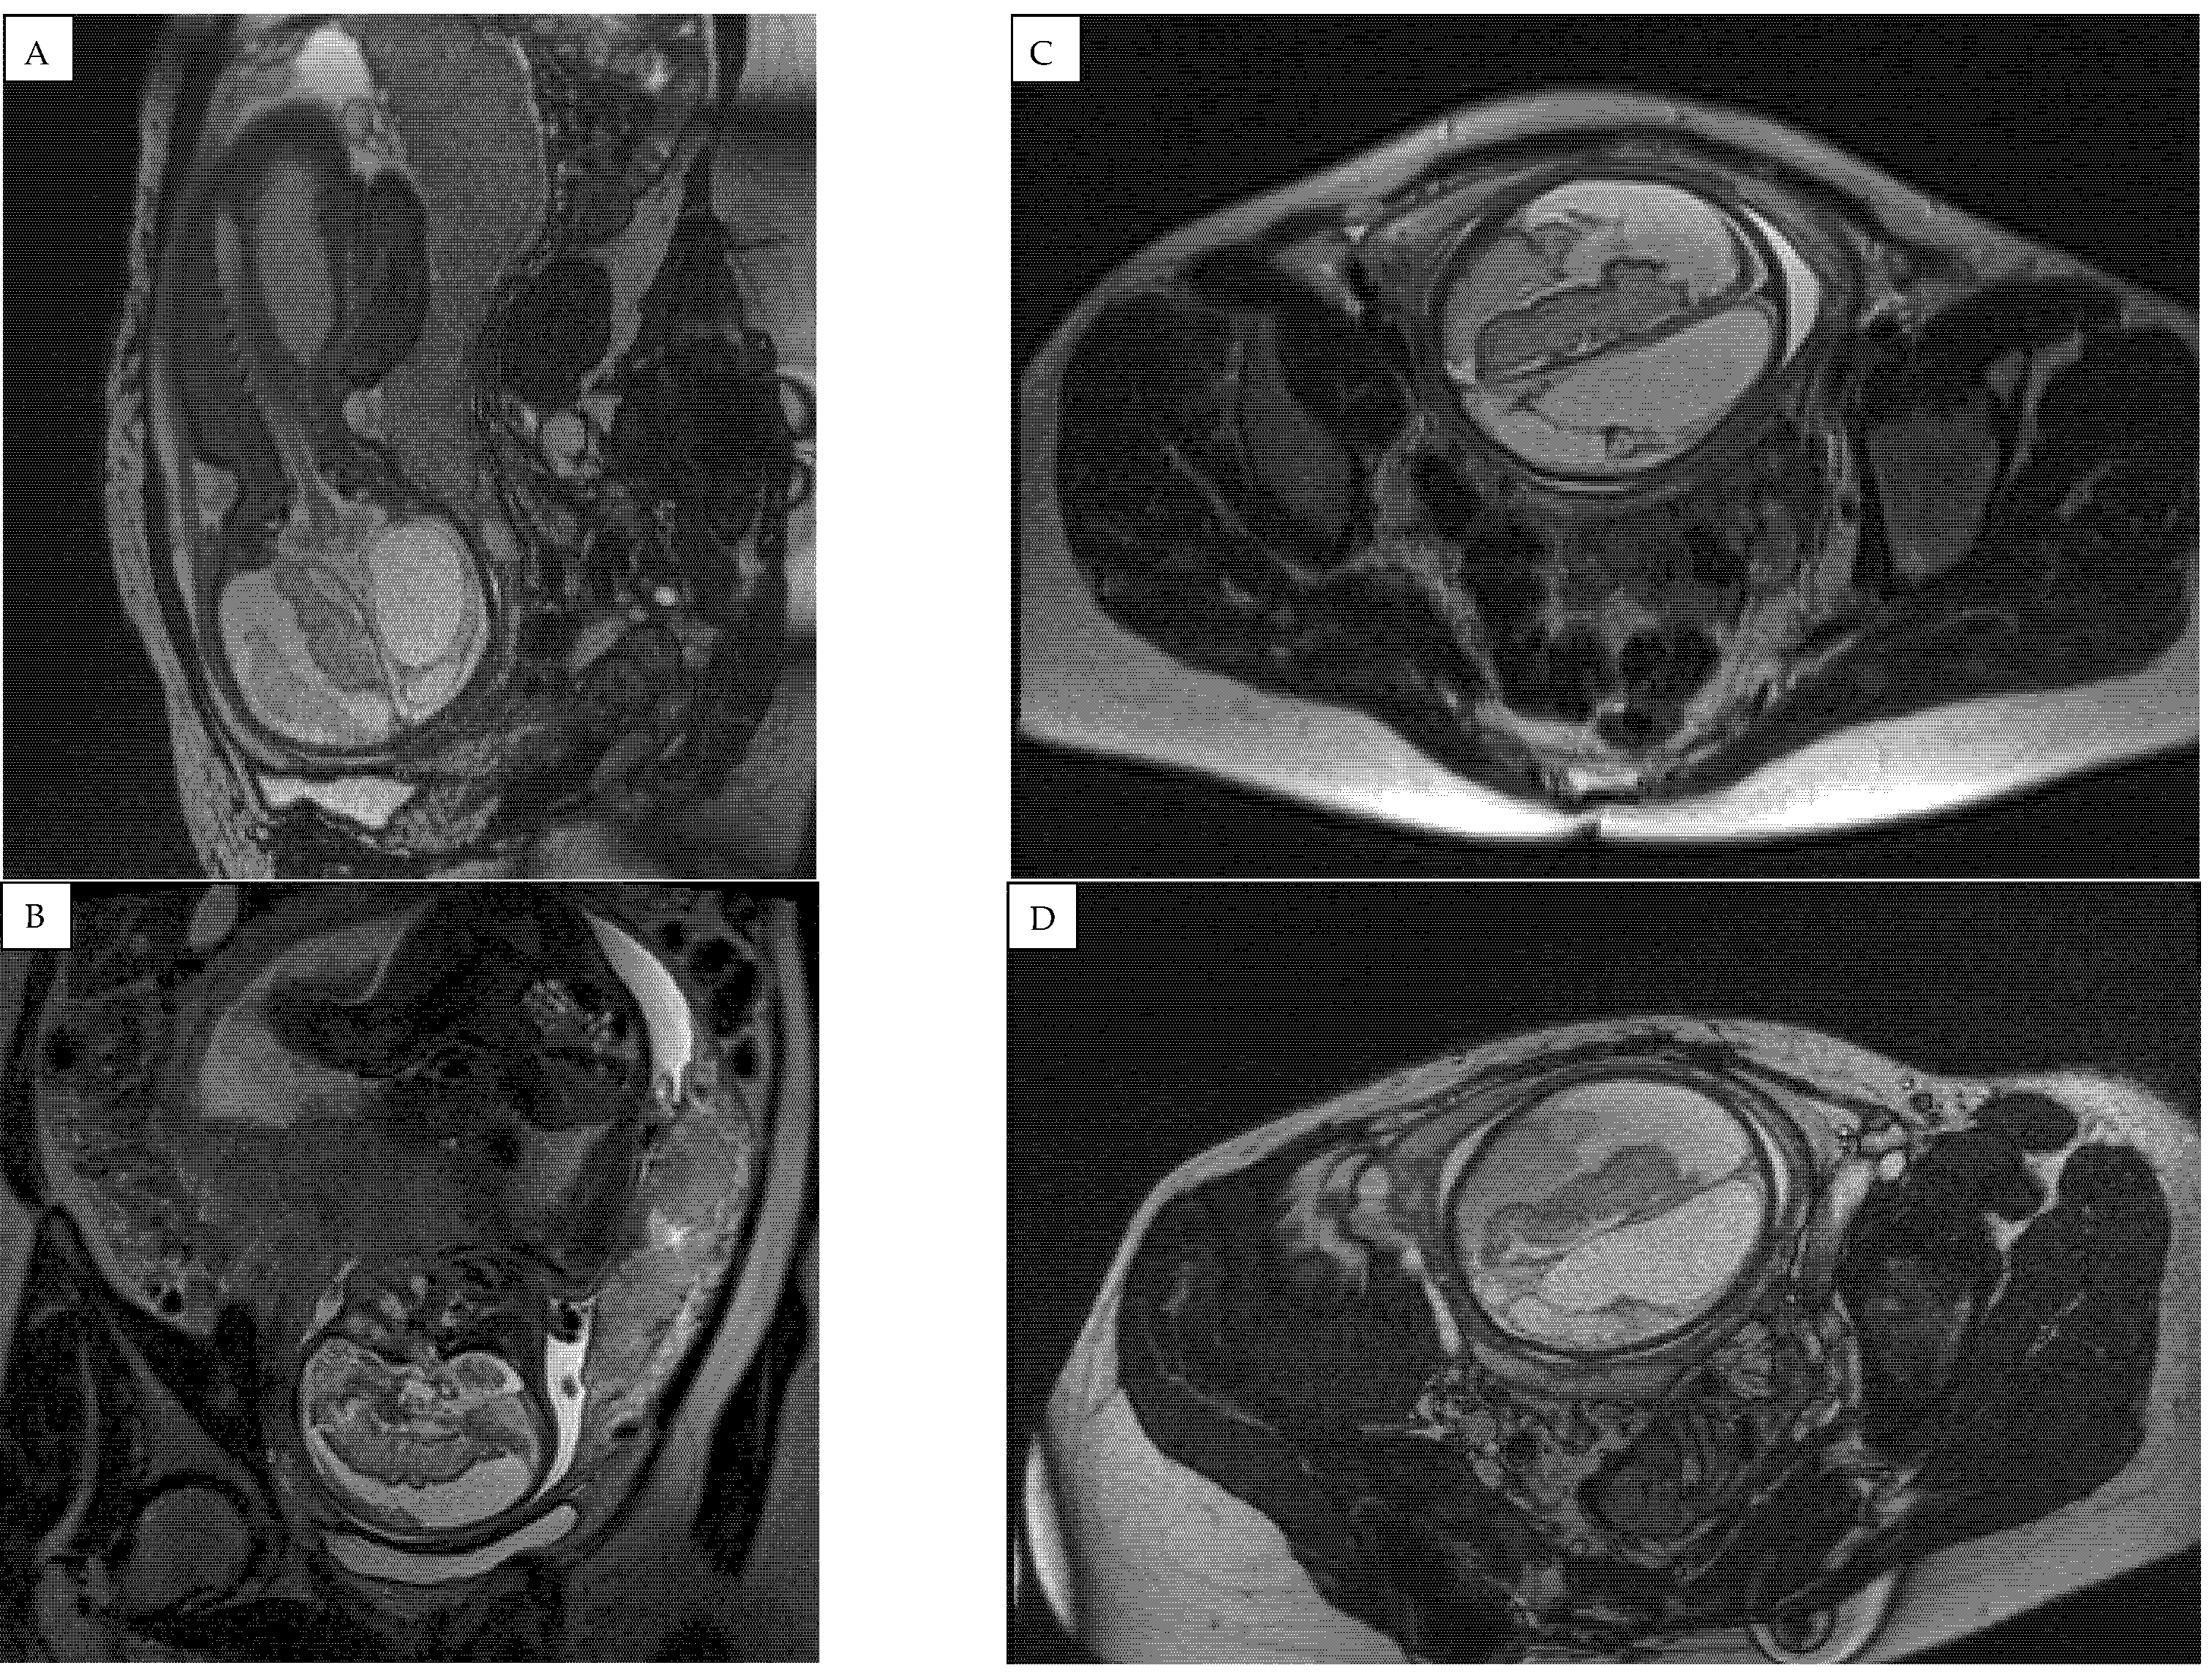

A fetal MRI test at 31 weeks demonstrated negative dynamics compared to 3 weeks prior (Figure 5). The right subdural space significantly expanded, the compression of the right hemisphere of the brain increased, and an image of emerging hygroma was observed. Hydrocephalus, likely occlusive, with dilatation of the left lateral ventricle and compression/atrophy of the cerebral parenchyma of left hemisphere, developed. A decreased volume of cerebellar parenchyma due to signs of emerging external paracerebellar hydrocephalus was observed. The midline remained shifted to the left for 6 (8–9) mm.

Figure 5.

Fetal magnetic resonance imaging (MRI) findings at 31 weeks of pregnancy showing significantly enlarged right subdural space and hygroma formation. (A) saggital, (B) coronal and (C), (D) transverse plane magnetic resonance images showing an occlusive hydrocephalus with dilatation of left ventricle and compression of cerebral parenchyma of left hemisphere with decreased cerebellar parenchyma.